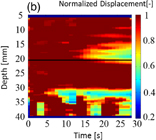

Standard image High-resolution imageFigure 9 shows the results from 49 data sets. The horizontal and vertical axes are coagulation size measured with a ruler after HIFU ablation and estimated by LMI, respectively. The closer the data point to the diagonal line are estimated with higher accuracy.

Fig. 9. Results of coagulation sizes measured with a ruler and estimated by LMI.

To evaluate the detection sensitivity of LMI with an AM frequency of 168 Hz, root mean square errors (RMSEs) were calculated for each data section. The RMSE that indicates the reliability index is described as

where Xi is the measured coagulation size, xi is an estimated coagulation size, and n is the number of sample. The results of RMSE and sample numbers in each data section are shown in Fig. 14. Figure 14 shows that region of the actual coagulation size does not correspond to the estimated coagulation size in the area of small coagulation sizes. Tissue deformation magnitude corresponds to the average tissue stiffness in the oscillated region. Therefore, when the coagulated region was smaller than the oscillated region, the RMSE was large. On the other hand, LMI can measure tissue deformation only in oscillated regions. Therefore, the RMSE was also large when the coagulated region was larger than the oscillated region.

Fig. 14. LMI accuracy in each data section.

Standard image High-resolution imageThe RMSE has a small value in the data section for 8–12 mm. In this section, LMI has a high sensitivity for detecting tissue coagulation. Even if the coagulation size is close to that of the oscillated region, there is variability. As a result, the current LMI measurement accuracy has an absolute error of approximately 2 mm. Furthermore, the average of all relative errors in this data section was 16%. In these experiments, the same tissue samples were used to compare actual lesion size directly with estimated size without variation among the samples. Therefore, the accuracy is a measurement error in LMI due to the disturbance of the oscillation caused by tissue heterogeneity, such as the presence of blood vessels.